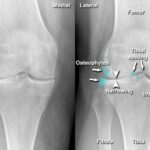

- Your X-rays show joint damage or bone-on-bone contact